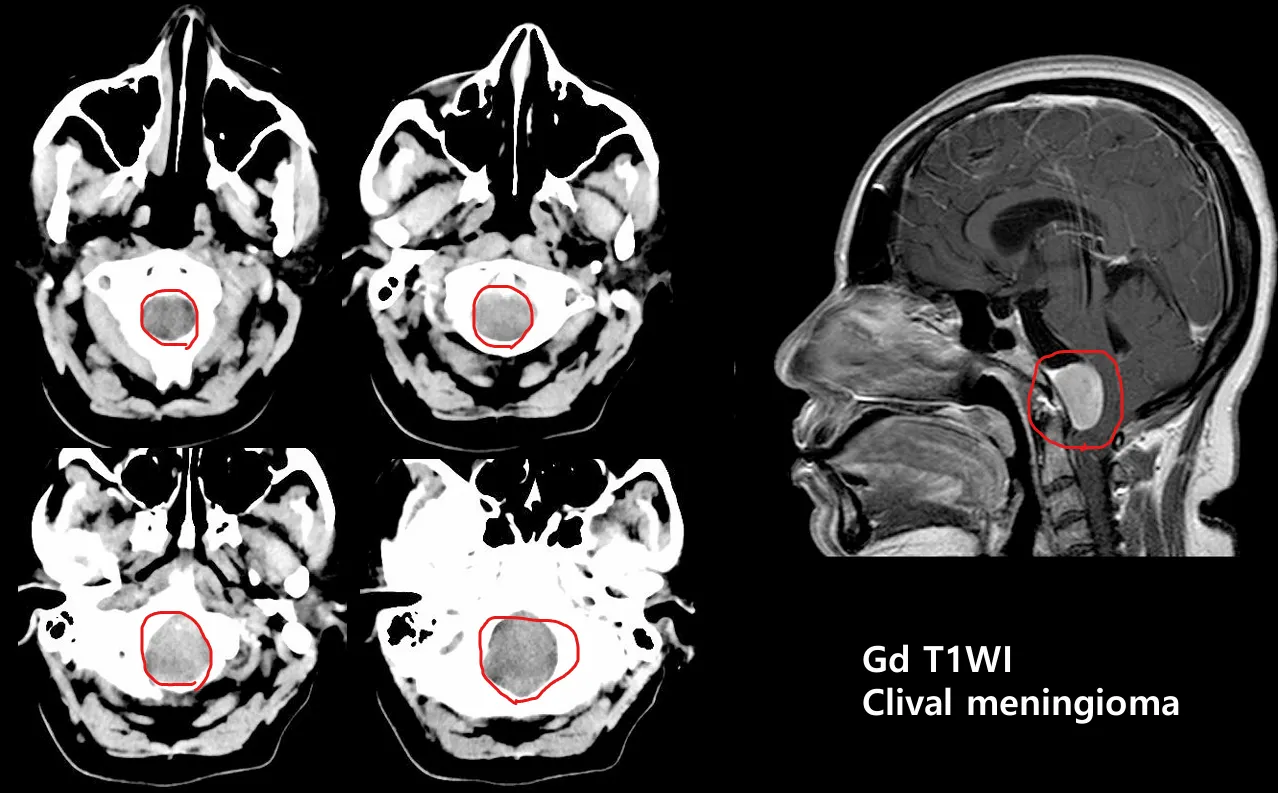

(해설) 판독과정에서 Brain조직이 거의 포함되지 않는 처음 사진과 끝 사진은 제대로 안 보고 넘어가는 경우가 더러 있다. Brain CT이긴 하지만 Brain 외의 구조물도 CT에는 촬영되며, 이 구조물까지 포함해서 항상 마지막 사진까지 꼼꼼하게 확인하는 습관을 들여야 한다. 아래 사진의 사례를 확인하자

Bottom cut에서는 Foramen magnum, central skull base, C1, C2를 확인한다.

이 사례에서는 foramen magnum 레벨에서 cisternal space가 보이지 않는다.

MRI를 촬영해 봤더니 Meningioma가 발견되었다.